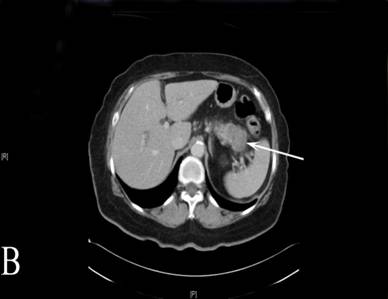

A 68-year-old woman presented with a three-month history of worsening abdominal pain, weight loss and jaundice. She had been diagnosed with type 2 diabetes three months prior to onset of symptoms. The patient’s past medical history included hypertension, asthma, diverticular disease, hypothyroidism, and a previous cholecystectomy. A CT and MRI scan of the abdomen showed an obstructing mass within the uncinate process of the pancreas and a second infiltrative mass in the tail of the pancreas encasing the splenic vein (Figure 2A, 2B). The uncinate process mass was causing a clear “double-duct” sign. An ERCP was attempted, but it failed and a percutaneous transhepatic biliary drain was inserted to relieve the jaundice prior to surgery. Her CA 19-9 was also negative. Both pancreatic tumours appeared resectable and following an MDT discussion a total pancreatectomy was performed. On pathology, both lesions proved to be necrotic masses with granulomatous inflammation and vasculitis, involving the common bile duct (the central one). Ziehl-Neelsen staining for mycobacteria and PAS for fungi was negative. Again, WG was considered the most likely cause for the observed histological features. CT of facial sinuses and lung function tests were again normal. She was p-ANCA positive (Anti MPO Ab= 8.8u/mL; normal range<3.4u/mL). There was no history of photosensitive rash, mouth ulcers or Raynaud’s disease. She has suffered from some morning stiffness lasting a few hours, but has not had any nosebleeds, sinus congestion or nasal crusting.

Figure 2. A. CT image depicting a mass at the uncinate process of the pancreas. The white arrow shows the mass. The white arrow head shows a cyst of the left kidney. B. CT image from the same patient showing the second mass at the tail of the pancreas in close proximity with vessels of the splenic hilum. The white arrow shows the mass. |